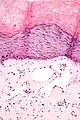

Histology

Angiokeratomas characteristically have large dilated blood vessels in the superficial dermis and hyperkeratosis (overlying the dilated vessels).

Scrotal angiokeratoma; visible large dilated blood vessels and hyperkeratosis